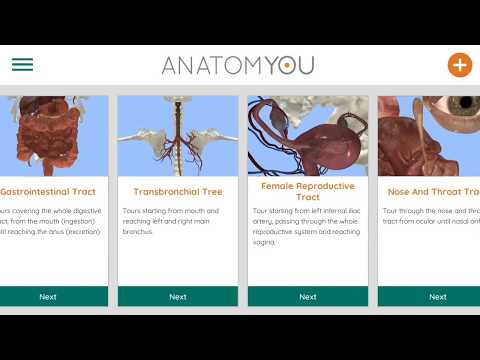

باستخدام الواقع الافتراضي ، سوف تكون قادرًا على التنقل على طول الهياكل التشريحية ، لتصبح جزءًا من علم التشريح البشري: الجهاز الدوري ، والجهاز التنفسي ، والجهاز الهضمي ، والبولي ، الدموي ، والإناث.

يوفر الوصول المجاني لبعض طرق الملاحة في أي من الأنظمة المذكورة تقريبًا. يتم تقديم محتوى إضافي يمكن شراؤه في قسم متجر التطبيقات داخل التطبيق.

يمكن استخدام Anatomyou VR في وضعين مختلفين: الواقع الافتراضي وملء الشاشة.